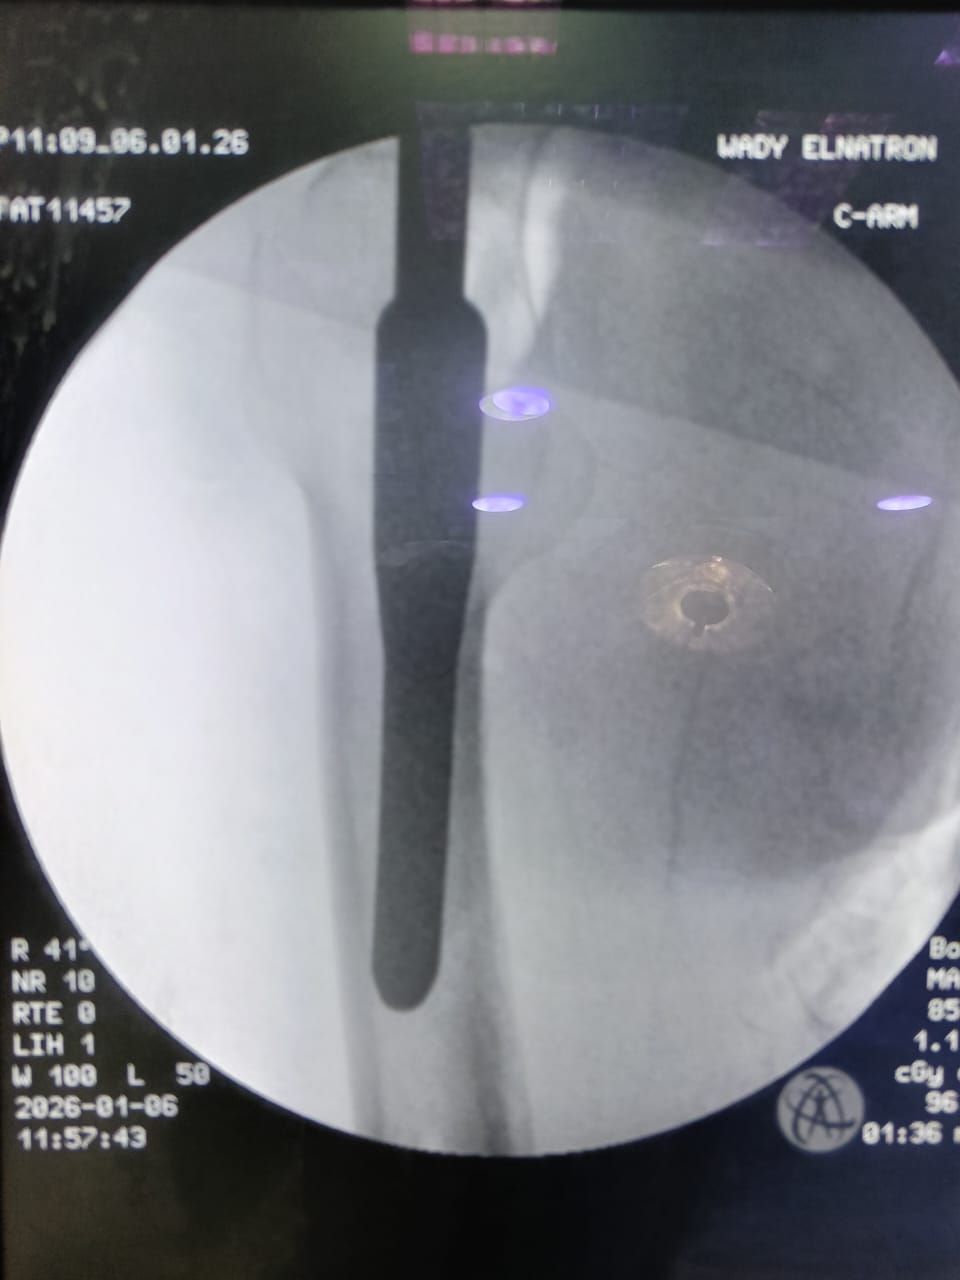

وعقب استقبال الحالة، تم إجراء التقييم الإكلينيكي الشامل والفحوصات الطبية اللازمة، وعلى ضوء النتائج تقرر التدخل الجراحي العاجل، حيث تم إجراء رد مغلق وتثبيت لكسر أعلى الفخذ الأيمن بين المدورين باستخدام مسمار نخاعي تشابكي (جاما نيل) المخصص لمثل هذه الكسور، بما يحقق ثباتًا جيدًا للكسر، ويساهم في سرعة التعافي وتقليل فرص حدوث المضاعفات.

وقد أُجريت العملية بنجاح من خلال الفريق الطبي:

دكتور/ طارق خيري علوي (استشاري جراحة العظام والكسور)

دكتور/ محمد أحمد عزب (نائب جراحة العظام والكسور)